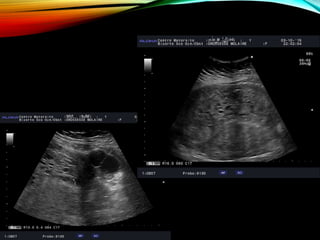

ECHOGRAPHIE

IMAGERIE

• #16 MASSE INTRACAVITAIRE CONTENANT DE NOMBREUX MICROKYSTES SANS IMAGE EMBRYONNAIRE ET SANS INVASION DU MYOMETRE (PAS DE DOPPLER DANS LA MASSE) +/- ASPECT D’OVAIRES MULTIFOLLICULAIRES (+/ HEMORRAGIQUES)